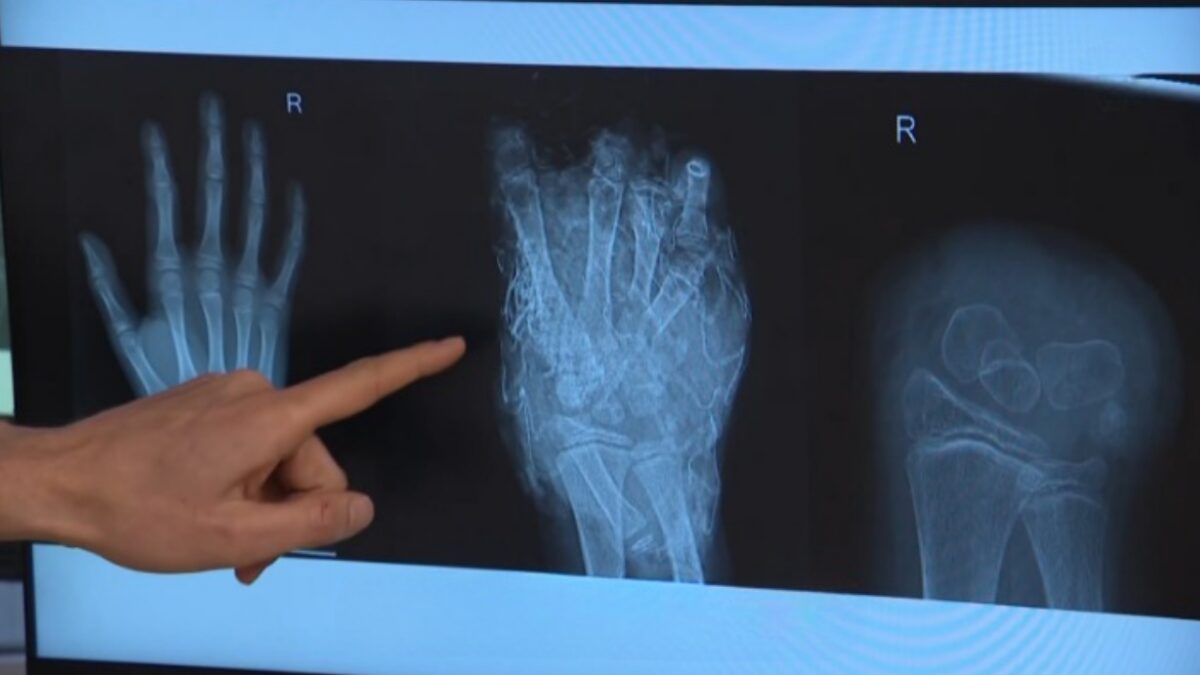

Ernstige letsels, vaak bij kinderen

Volgens VeiligheidNL liepen twintig mensen zulke zware verwondingen op dat amputatie nodig was. Twee mensen kwamen om het leven door vuurwerk, in Nijmegen en Aalsmeer. In november viel ook in Groningen al een dode. Meer dan de helft van alle slachtoffers was jonger dan twintig jaar.